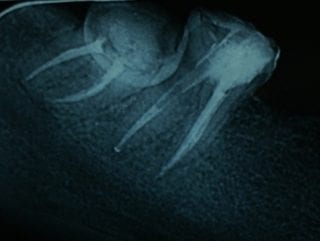

Radiografii postoperatorii 4.5, 4.7:

Pe canalul distal al molarului 4.7 se observă radiotransparența dată de pivotul din fibră de sticlă aplicat pe canalul distal după obturare:

La nivelul molarilor au fost identificate cate 2 canale meziale si un canal distal. Radiologic canalele meziale se suprapun.